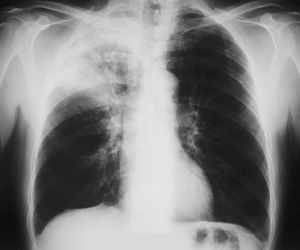

Εικόνα 1

Οπισθιο-πρόσθια ακτινογραφία θώρακος. Πυκνοατελεκτασία με φλεγμονώδη στοιχεία στον δεξιό άνω λοβό. Η βρογχοσκόπηση έδειξε ότι υπήρχε όγκος στο στόμιο του λοβαίου βρόγχου του άνω λοβού που το απέφρασσε πλήρως. Η βιοψία έδειξε ότι πρόκειται για πλακώδες καρκίνωμα πνεύμονος.